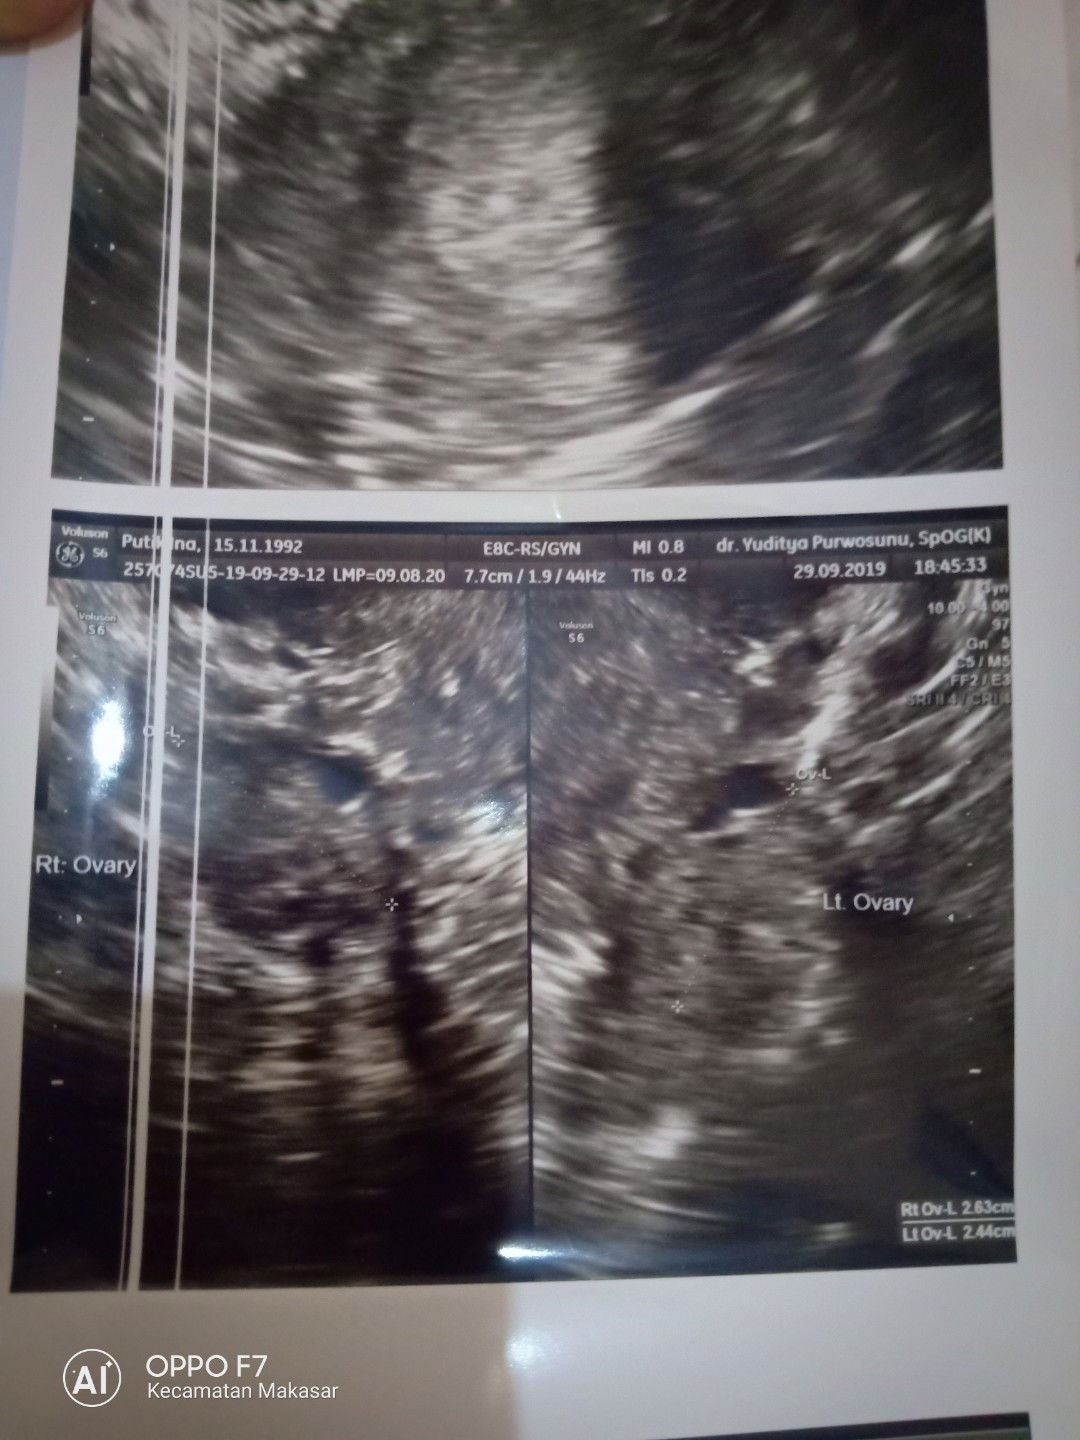

usg

Bunda mau tanya ada ga yg usia kehamilan nya berbeda di bidan udh masuk 6-7 minggu tp pas d usg baru 4-5 minggu itu pun baru keliatan kantong kecil bgt, Masih normal kah?? Kepikiran d suruh usg 3 minggu lg ? Share pengalaman kalian ya bun